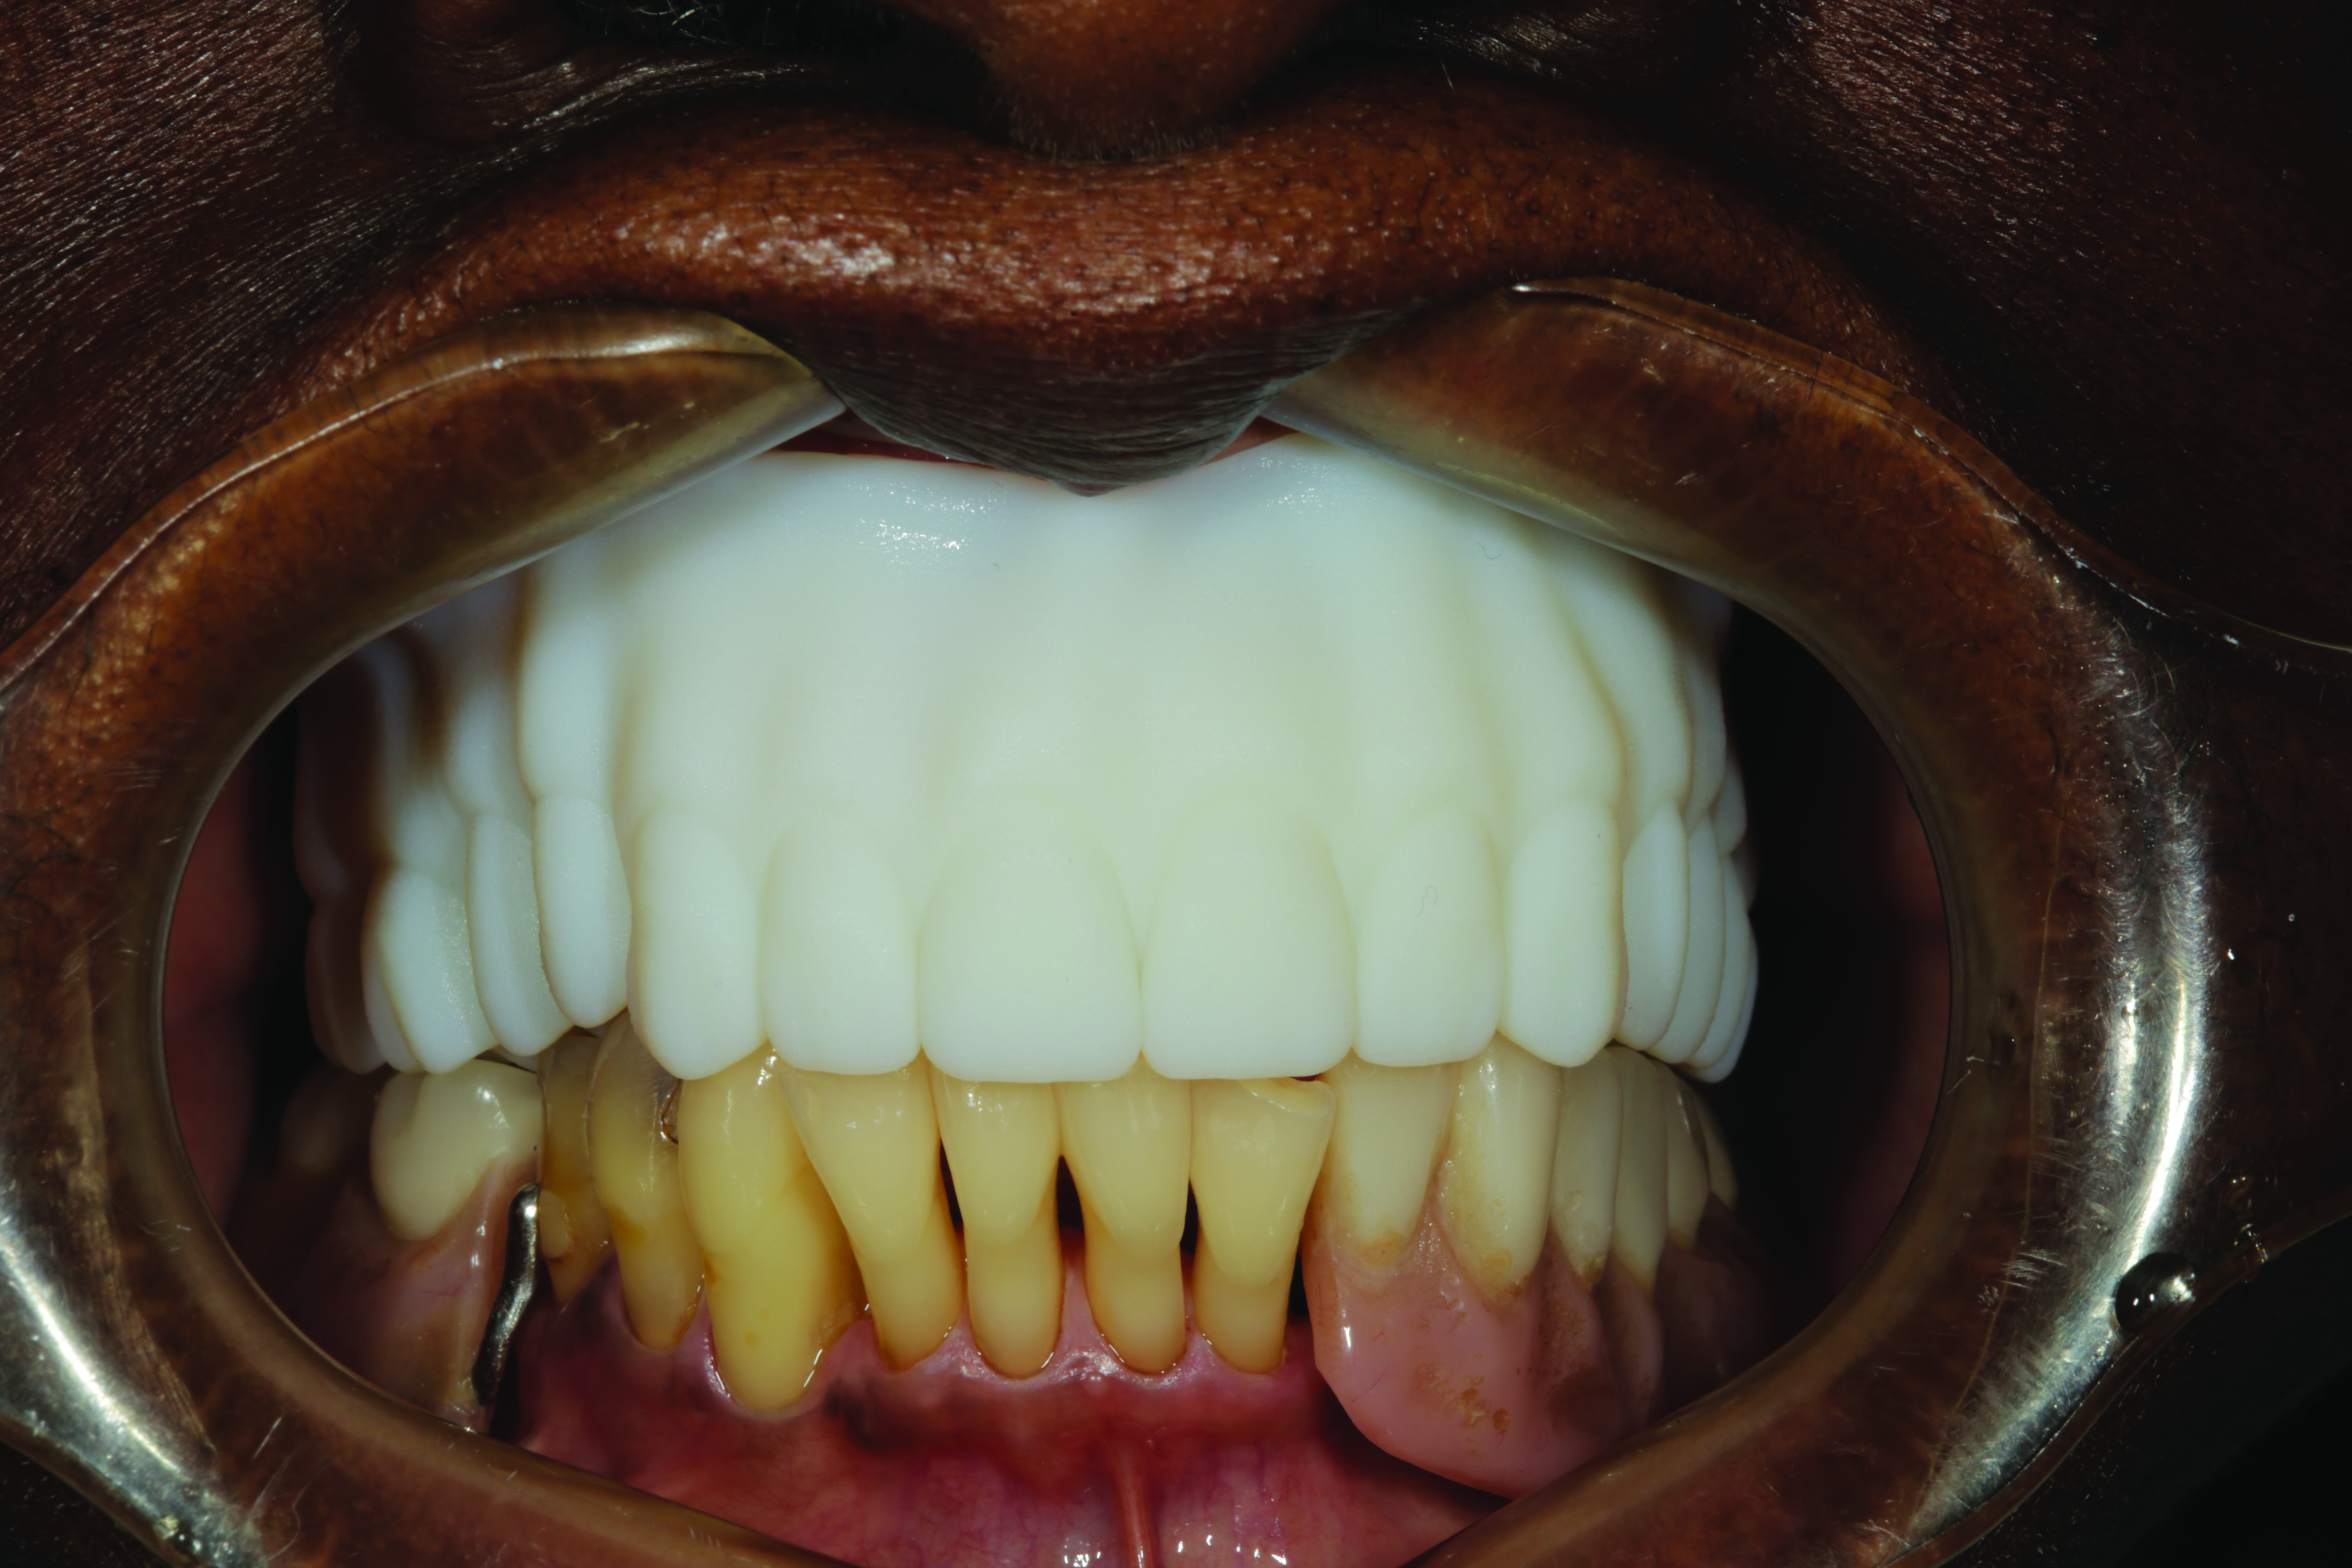

Upon delivery of the case, the same parameters of retention, VDO, esthetics, phonetics, and occlusion were evaluated. Minor adjustments to occlusion were accomplished using articulating paper and acrylic burs to ensure maximum intercuspation in centric occlusion (Figure 5).

Fig 5. Minor adjustments to occlusion are accomplished using articulating paper and acrylic burs to ensure maximum intercuspation in centric occlusion.

Figure 5